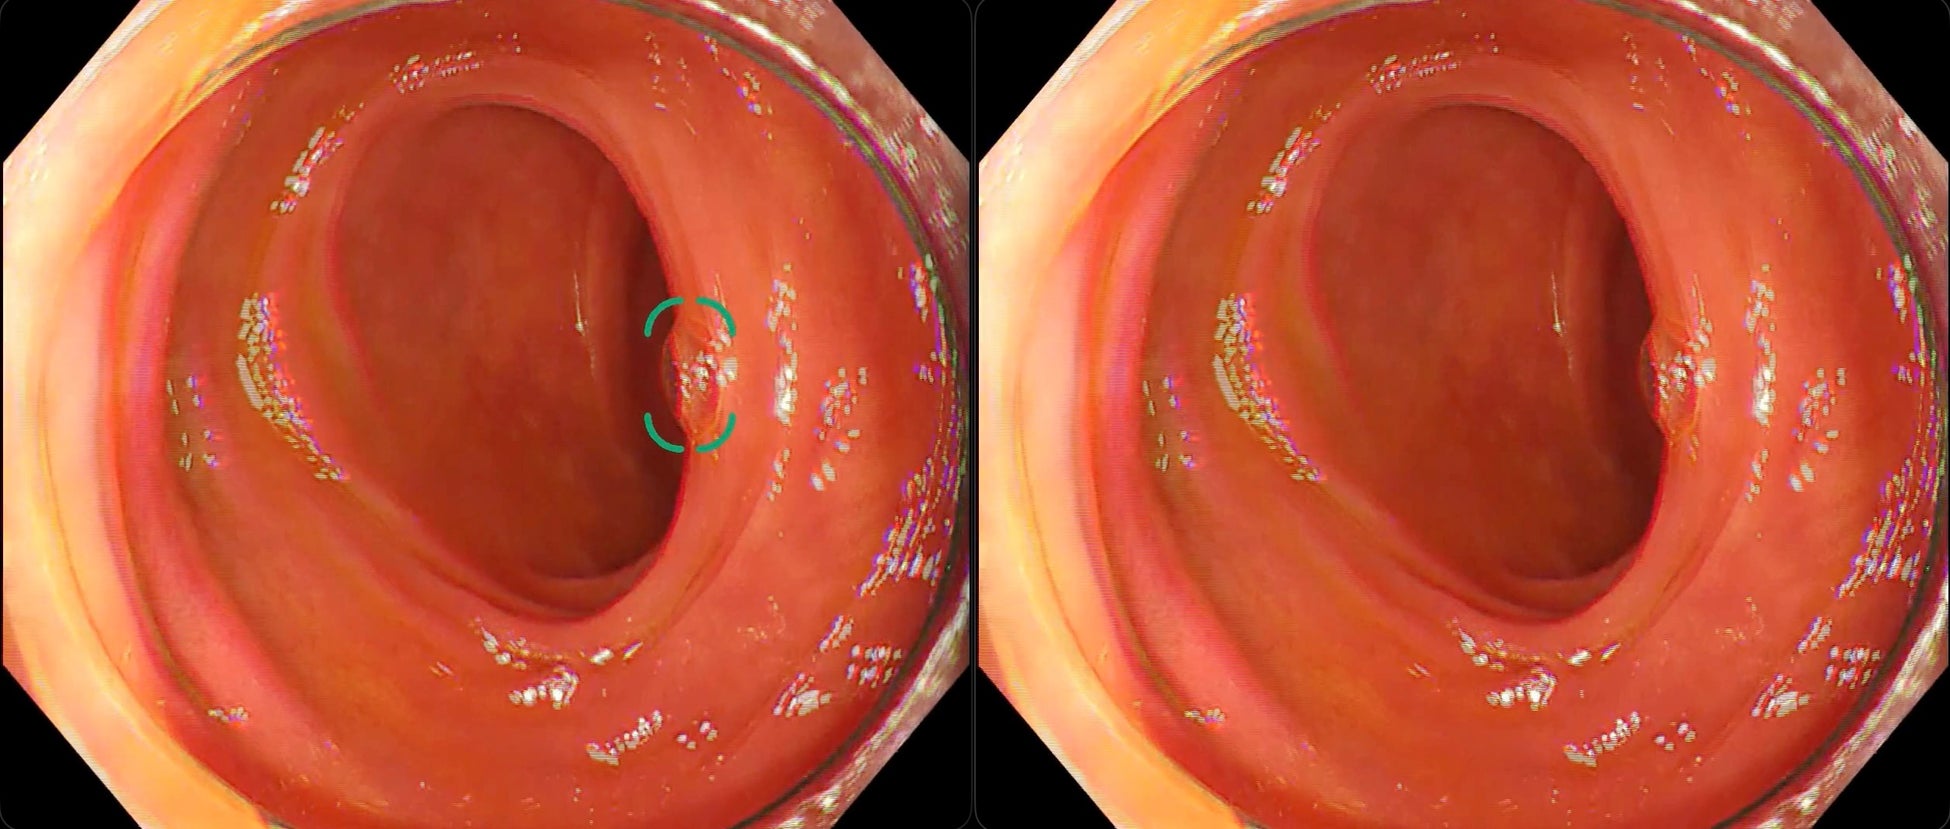

【検出事例】新旧モデル比較(左:旧モデル、右:新モデル)

③ 泡による偽陽性が改善した例

※いずれの検出例もイメージであり、実際の製品表示とは異なる場合があります。